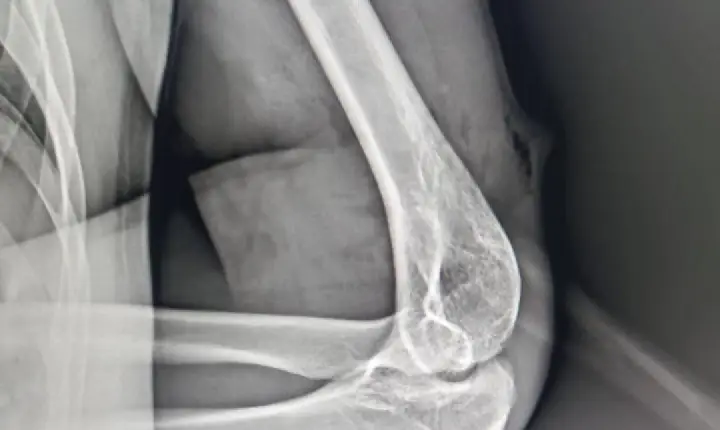

Lasca de madeira atravessa braço de homem durante manutenção de ponte em Paranatinga

De acordo com informações obtidas pelo Jornal Paranatinga em Destaque um trabalhador, identificado como Vanderson de Araújo, fazia manutenção em uma ponte de madeira na Aldeia Aturua quando o acidente aconteceu. Uma tora de madeira teria lascado e perfurado o braço do homem.

Vanderson não precisou ser levado para Rondonópolis para fazer a retirada do material conforme informado a reportagem inicialmente. A retirada foi feita com sucesso no centro cirúrgico do hospital municipal Irmã Teodora em Paranatinga, sem lesão nervosa, óssea ou vascular.

O paciente passa bem, segue com braço enfaixado, medicado e em observação.